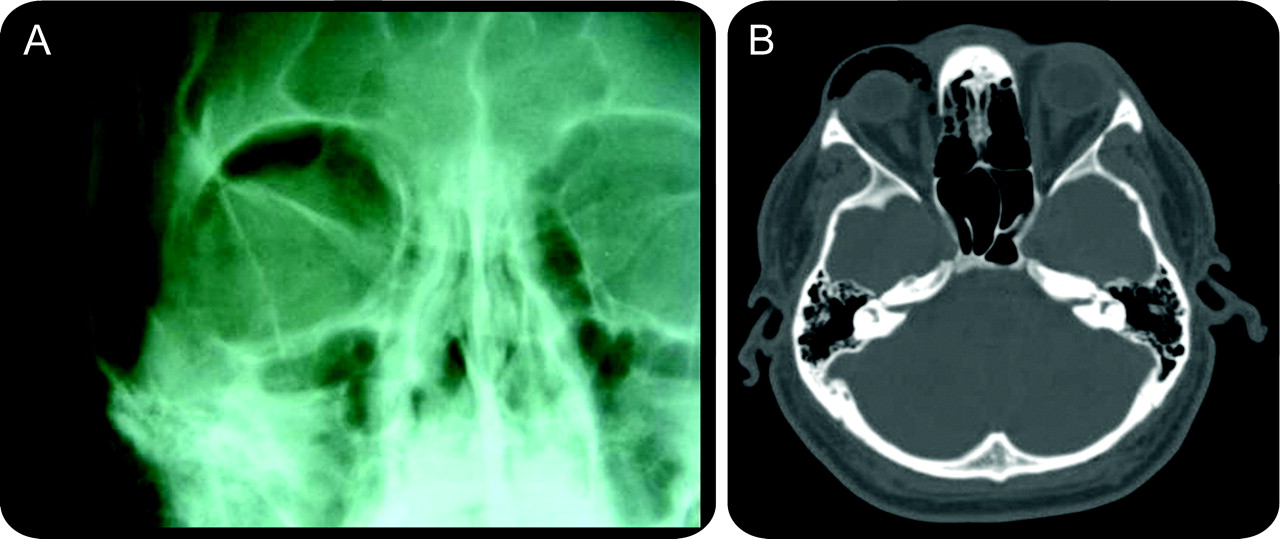

轨道肺气肿后鼻子吹